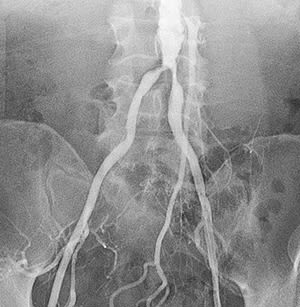

Peripheral Angiography

Peripheral angiography is a test that uses X-ray and dye (contrast material) to map the blood vessels (arteries) in your lower body, legs, and arms. This map can show where blood flow may be blocked.